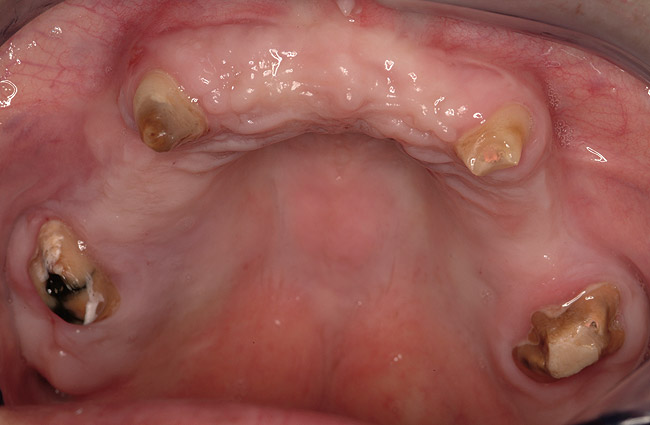

Figure 3  Pre-extraction situation. Tooth Nos. 24 and 25 were planned for extraction, and simultaneous ridge augmentation was planned. Implant placement in these two positions at the conclusion of active tooth movement was also planned.

Figure 3